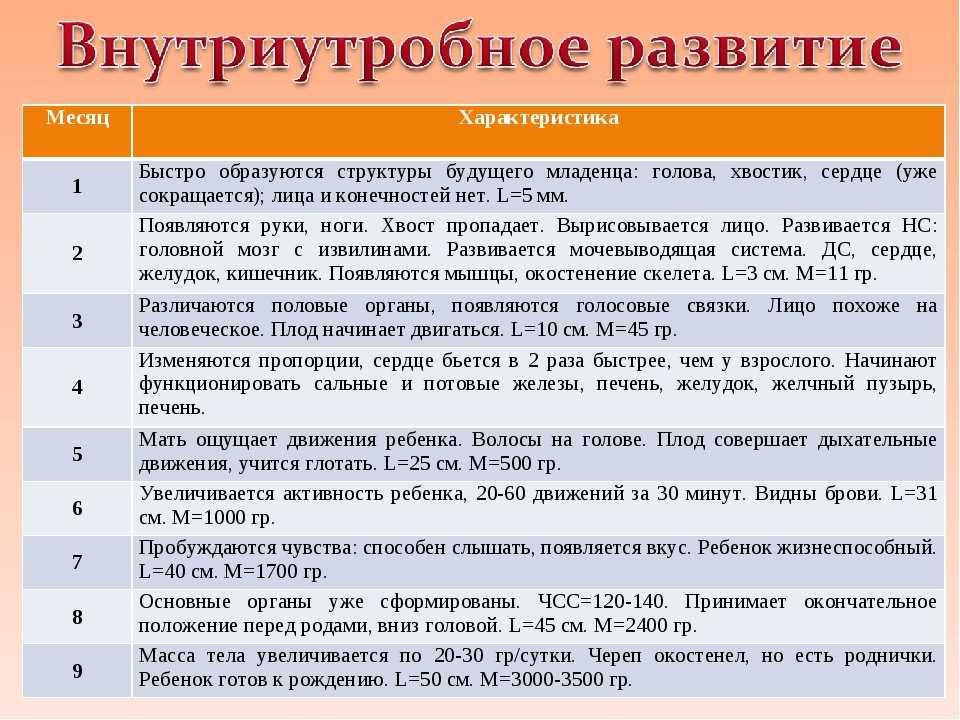

По окончании второго триместра будущая мамочка выходит на финишную прямую. Впереди только роды и счастливые годы материнства. Таких крупных перемен уже не будет, каждый следующий месяц ребенок будет все больше и больше готовиться к появлению на свет: набирать вес (в 9 месяцев ребенок весит – более 3 килограмм), сформируется его собственная система регуляции тепла, которая не даст ему замерзнуть при появлении на свет, окончательно разовьются легкие, чтобы позволить малышу легко перейти к новому виду дыхания.

16 недель. Ребенок весит примерно 150 граммов, его рост достигает 16-18 сантиметров. На головке появляются волосы, на лице — реснички и брови. Малыш открывает ротик, глотает, сосет, улыбается. В этот период начинает полноценно функционировать плацента, которая связывает его с мамой.

20 недель. Рост малыша достигает 30 сантиметров, у него появляются ноготки на пальцах рук и ног. Теперь мама чувствует его движения, так как время от времени он начинает заниматься физкультурой: отталкивается от одной стенки матки и доплывает до другой. Кроме того, ребенок может отреагировать на резкий звук или волнение матери прыжком, который воспринимается как активное шевеление. Если же малыш начинает икать, женщина ощущает слабые ритмичные толчки, идущие изнутри. В 20 недель врачи выслушивают сердцебиение малыша с помощью стетоскопа.

24 недели. Малыш уже может рассердиться. Это доказывает фотография ребенка в этом возрасте. На ней видны его сердитый взгляд, напряжение мышц вокруг глаз, сморщенные губки, видно, что он плачет, выражая свое недовольство. Кстати, чтобы отдохнуть ночью, малыш ложится спать и… видит сны. Ребенок весит около 500 граммов это немного, но он только начал набирать вес. Его кожа красная и морщинистая. Так как она еще очень нежна, малыш защищается от воздействия околоплодных вод специальной смазкой. К 24-й неделе беременности начинают функционировать жировые и потовые железы, созревают легкие ребенка. В них образуется пленка, которая не дает им склеиваться при дыхании. Если ребенок родится в это время и будет обеспечен необходимой заботой, он сможет выжить.

8-й месяц: 29-32 недели

С каждым днем ребенок все больше и больше подготавливается к предстоящей жизни вне организма мамы и родам. Он уже весит около 1,5-1,6 килограмма и достигает в длину 40 сантиметров. Сейчас он занимает почти все место в матке, поэтому движения его очень рациональны. Он уже не «плавает», а совершает более точные движения ручками и ножками.

В течение 8-го месяца ребенок занимает то положение, в котором он будет в родах.

В 96% случаев – это головное предлежание – то есть ребенок располагается строго головой вниз, бывает также тазовое предлежание – когда он занимает позицию попкой или ножками к выходу из малого таза, а также поперечное предлежание – когда он лежит поперек продольной оси матки.

Самым лучшим для естественных родов, конечно, является головное предлежание, но на 8-м месяце предлежание ребенка еще может поменяться само или с помощью специальных упражнений. Однако, если он уже устроился (головное предлежание), можете одевать бандаж, чтобы закрепить такое положение.

Ваш доктор, используя специальные приемы пальпации – приёмы Леопольда, может очень легко определить положение плода.

На 8-м месяце продолжают формироваться альвеолы легких, увеличивается количество сурфактанта.

Почти полностью формируется сердце и кровеносная система: между правым и левым предсердием пока остается отверстие (баталлов проток), поэтому в венах и артериях ребенка течет смешанная кровь. Это отверстие закроется уже после рождения.

10-й месяц: 37-40 недель

Не переживайте если ребенок не родился на 9-м месяце, у него еще есть время. Рождение в 37-42 недель абсолютно естественно и нормально. Вы должны довериться в этом ребенку и своему мудрому организму, они сами подберут наилучшее время.

Итак, на 10-м месяце все системы ребенка готовы к рождению. Работает пищеварительный тракт: ворсинки кишечника продвигают первородный кал вниз к толстому кишечнику, работает желудок, поджелудочная железа вырабатывает пепсин, необходимый в пищеварении.

Однако пищеварительная система ребенка в утробе абсолютно стерильна, все нужные бактерии, которые помогают переваривать и усваивать пищу появятся только в период лактации из грудного молока матери.

Заканчивает развитие половая система – у девочек большие половые губы закрывают маленькие, у мальчиков яички в большинстве случаев опускаются в мошонку.

Надпочечники настолько увеличиваются в размерах, что становятся больше почек, так как на их долю приходится выработка гормонов стресса во время родов – адреналина и норадреналина.

Кости черепа и швы остаются мягкими и податливыми. 2 родничка – теменной и затылочный помогают черепу принять удобную форму, чтобы пройти по родовым каналам матери без травм.